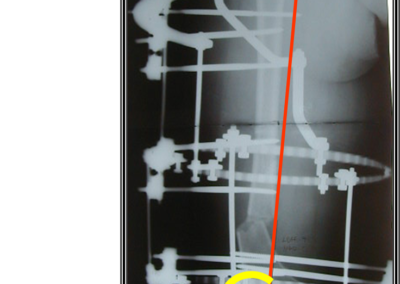

arthritis deformity surgery endoprosthesis hip prosthesis ilizarov ilizarov surgery infected nonunion knee prosthesis lengthening surgery limb lengthening surgery nonunion periprosthetic infection psodoartroz revision surgery total hip prosthesis total knee prosthesis